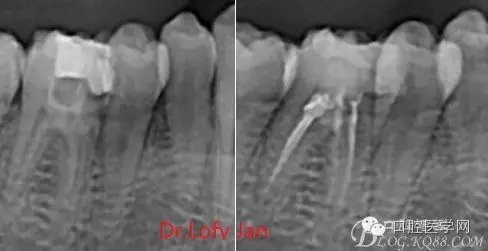

前言:自己做的一些曲面斷層片在未試尖根管治療中的病例整理,發(fā)現(xiàn)問題很多包括自身的,技術(shù)的,還有設(shè)備的問題,予以總結(jié)整理并期待進(jìn)一步提高。

根管治療術(shù)是牙體牙髓疾病治療中最復(fù)雜和最關(guān)鍵的治療項目。根管充填材料抵達(dá)根尖、并能嚴(yán)密堵塞根尖孔,是確保根管治療效果的關(guān)鍵指標(biāo)。為了保證根管充填到位,醫(yī)生需要在術(shù)前照牙片以了解牙根根管的數(shù)量、彎曲程度和長度,在術(shù)中有時需要插針照牙片來精確測量根管長度,術(shù)后必須照牙片以確定是否根管充填到位,如果欠填或超填,就需要重新充填、重新照牙片確認(rèn),直到根管充填到位。所以,在患者接受根管治療時有時會反復(fù)照牙片。

病例分析:曲面斷層片在x線輔助診斷與檢查中目前大多數(shù)文獻(xiàn)和著作都建議只能作為初診拍片檢查手段,不能作為終末疾病的確診與手術(shù)療效的評價指標(biāo),臨床大部分中小型門診都因為設(shè)備不齊全導(dǎo)致信息偏差很大。